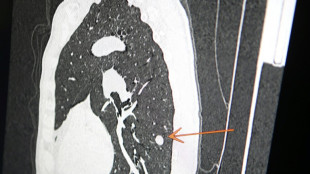

"Usted tiene cáncer", mensaje erróneo y aterrador a cientos de pacientes de una clínica en Inglaterra

Una clínica del norte de Inglaterra dio un gran susto a cientos de pacientes al enviar el mensaje "diagnóstico: cáncer de pulmón agresivo con metástasis" en lugar de sus buenos deseos de Navidad, informó el diario The Sun el jueves.